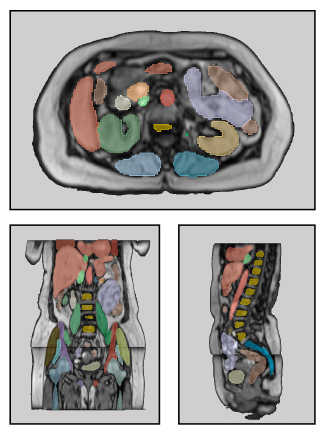

Purpose: To introduce a deep learning model capable of multi-organ segmentation in MRI scans, offering a solution to the current limitations in MRI analysis due to challenges in resolution, standardized intensity values, and variability in sequences. Materials and Methods: he model was trained on 1,200 manually annotated MRI scans from the UK Biobank, 221 in-house MRI scans and 1228 CT scans, leveraging cross-modality transfer learning from CT segmentation models. A human-in-the-loop annotation workflow was employed to efficiently create high-quality segmentations. The model's performance was evaluated on NAKO and the AMOS22 dataset containing 600 and 60 MRI examinations. Dice Similarity Coefficient (DSC) and Hausdorff Distance (HD) was used to assess segmentation accuracy. The model will be open sourced. Results: The model showcased high accuracy in segmenting well-defined organs, achieving Dice Similarity Coefficient (DSC) scores of 0.97 for the right and left lungs, and 0.95 for the heart. It also demonstrated robustness in organs like the liver (DSC: 0.96) and kidneys (DSC: 0.95 left, 0.95 right), which present more variability. However, segmentation of smaller and complex structures such as the portal and splenic veins (DSC: 0.54) and adrenal glands (DSC: 0.65 left, 0.61 right) revealed the need for further model optimization. Conclusion: The proposed model is a robust, tool for accurate segmentation of 40 anatomical structures in MRI and CT images. By leveraging cross-modality learning and interactive annotation, the model achieves strong performance and generalizability across diverse datasets, making it a valuable resource for researchers and clinicians. It is open source and can be downloaded from https://github.com/hhaentze/MRSegmentator.